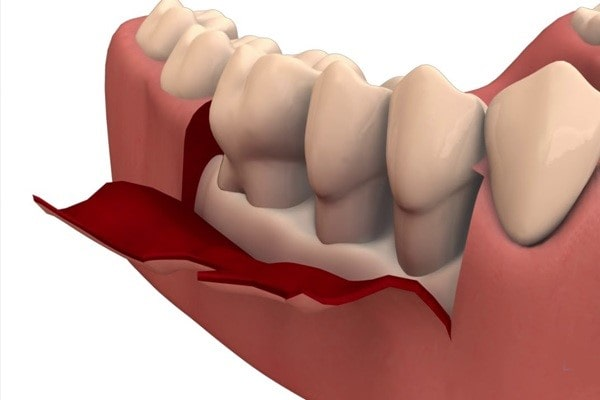

گروه هیچ یک زندگی – عقبرفتگی لثه یک مشکل تدریجی است و زمانی اتفاق میافتد که بافت لثه خودش را از روی دندان کنار میکشد و ریشه دندان در معرض قرار میگیرد. عقب رفتن لثه میتواند برای تمام دندانها یا فقط یک دندان اتفاق بیفتد.

گاهی تنها با نگاهکردن در آینه میتوانید عقبرفتگی لثه را ببینید و اگر خفیف باشد احتمالاً هیچ علامت دیگری ندارد. اما عقبرفتگی لثهای که شدیدتر است میتواند در نهایت منجر به دنداندرد و حساس شدن دندان و حتی لق شدن دندان شود.

بیماری لثه دارید

پلاک و تارتار میتواند در نهایت به زیر خط لثه نفوذ کند و باعث التهاب بیشتر لثه شده و بیماری لثه یا عفونت لثه ایجاد کند. این مشکل میتواند لثهها را قرمز و متورم و ملتهب کند و باعث عقبرفتگیشان بشود.

بیماری لثه بهمرورزمان تشدید شده و جویدن را دردناک میکند و حتی ممکن است دندان لق شده و بیفتد.

دندانهایی که کج شدهاند یا به هم فشرده شدهاند میتوانند به لثه آسیب بزنند. اگر یک ناهمترازی بین دندانها وجود داشته باشد، بافت لثهای که روی ریشه را پوشانده ممکن است در معرض آسیب و پارگی ناشی از فعالیتهایی مثل جویدن و مسواکزدن قرار بگیرد و در نتیجه لثه عقب برود.

. جراحی پیوند لثه که معمولاً شامل گرفتن بافتی از سقف دهان و چسباندن آن به خط لثه میشود.